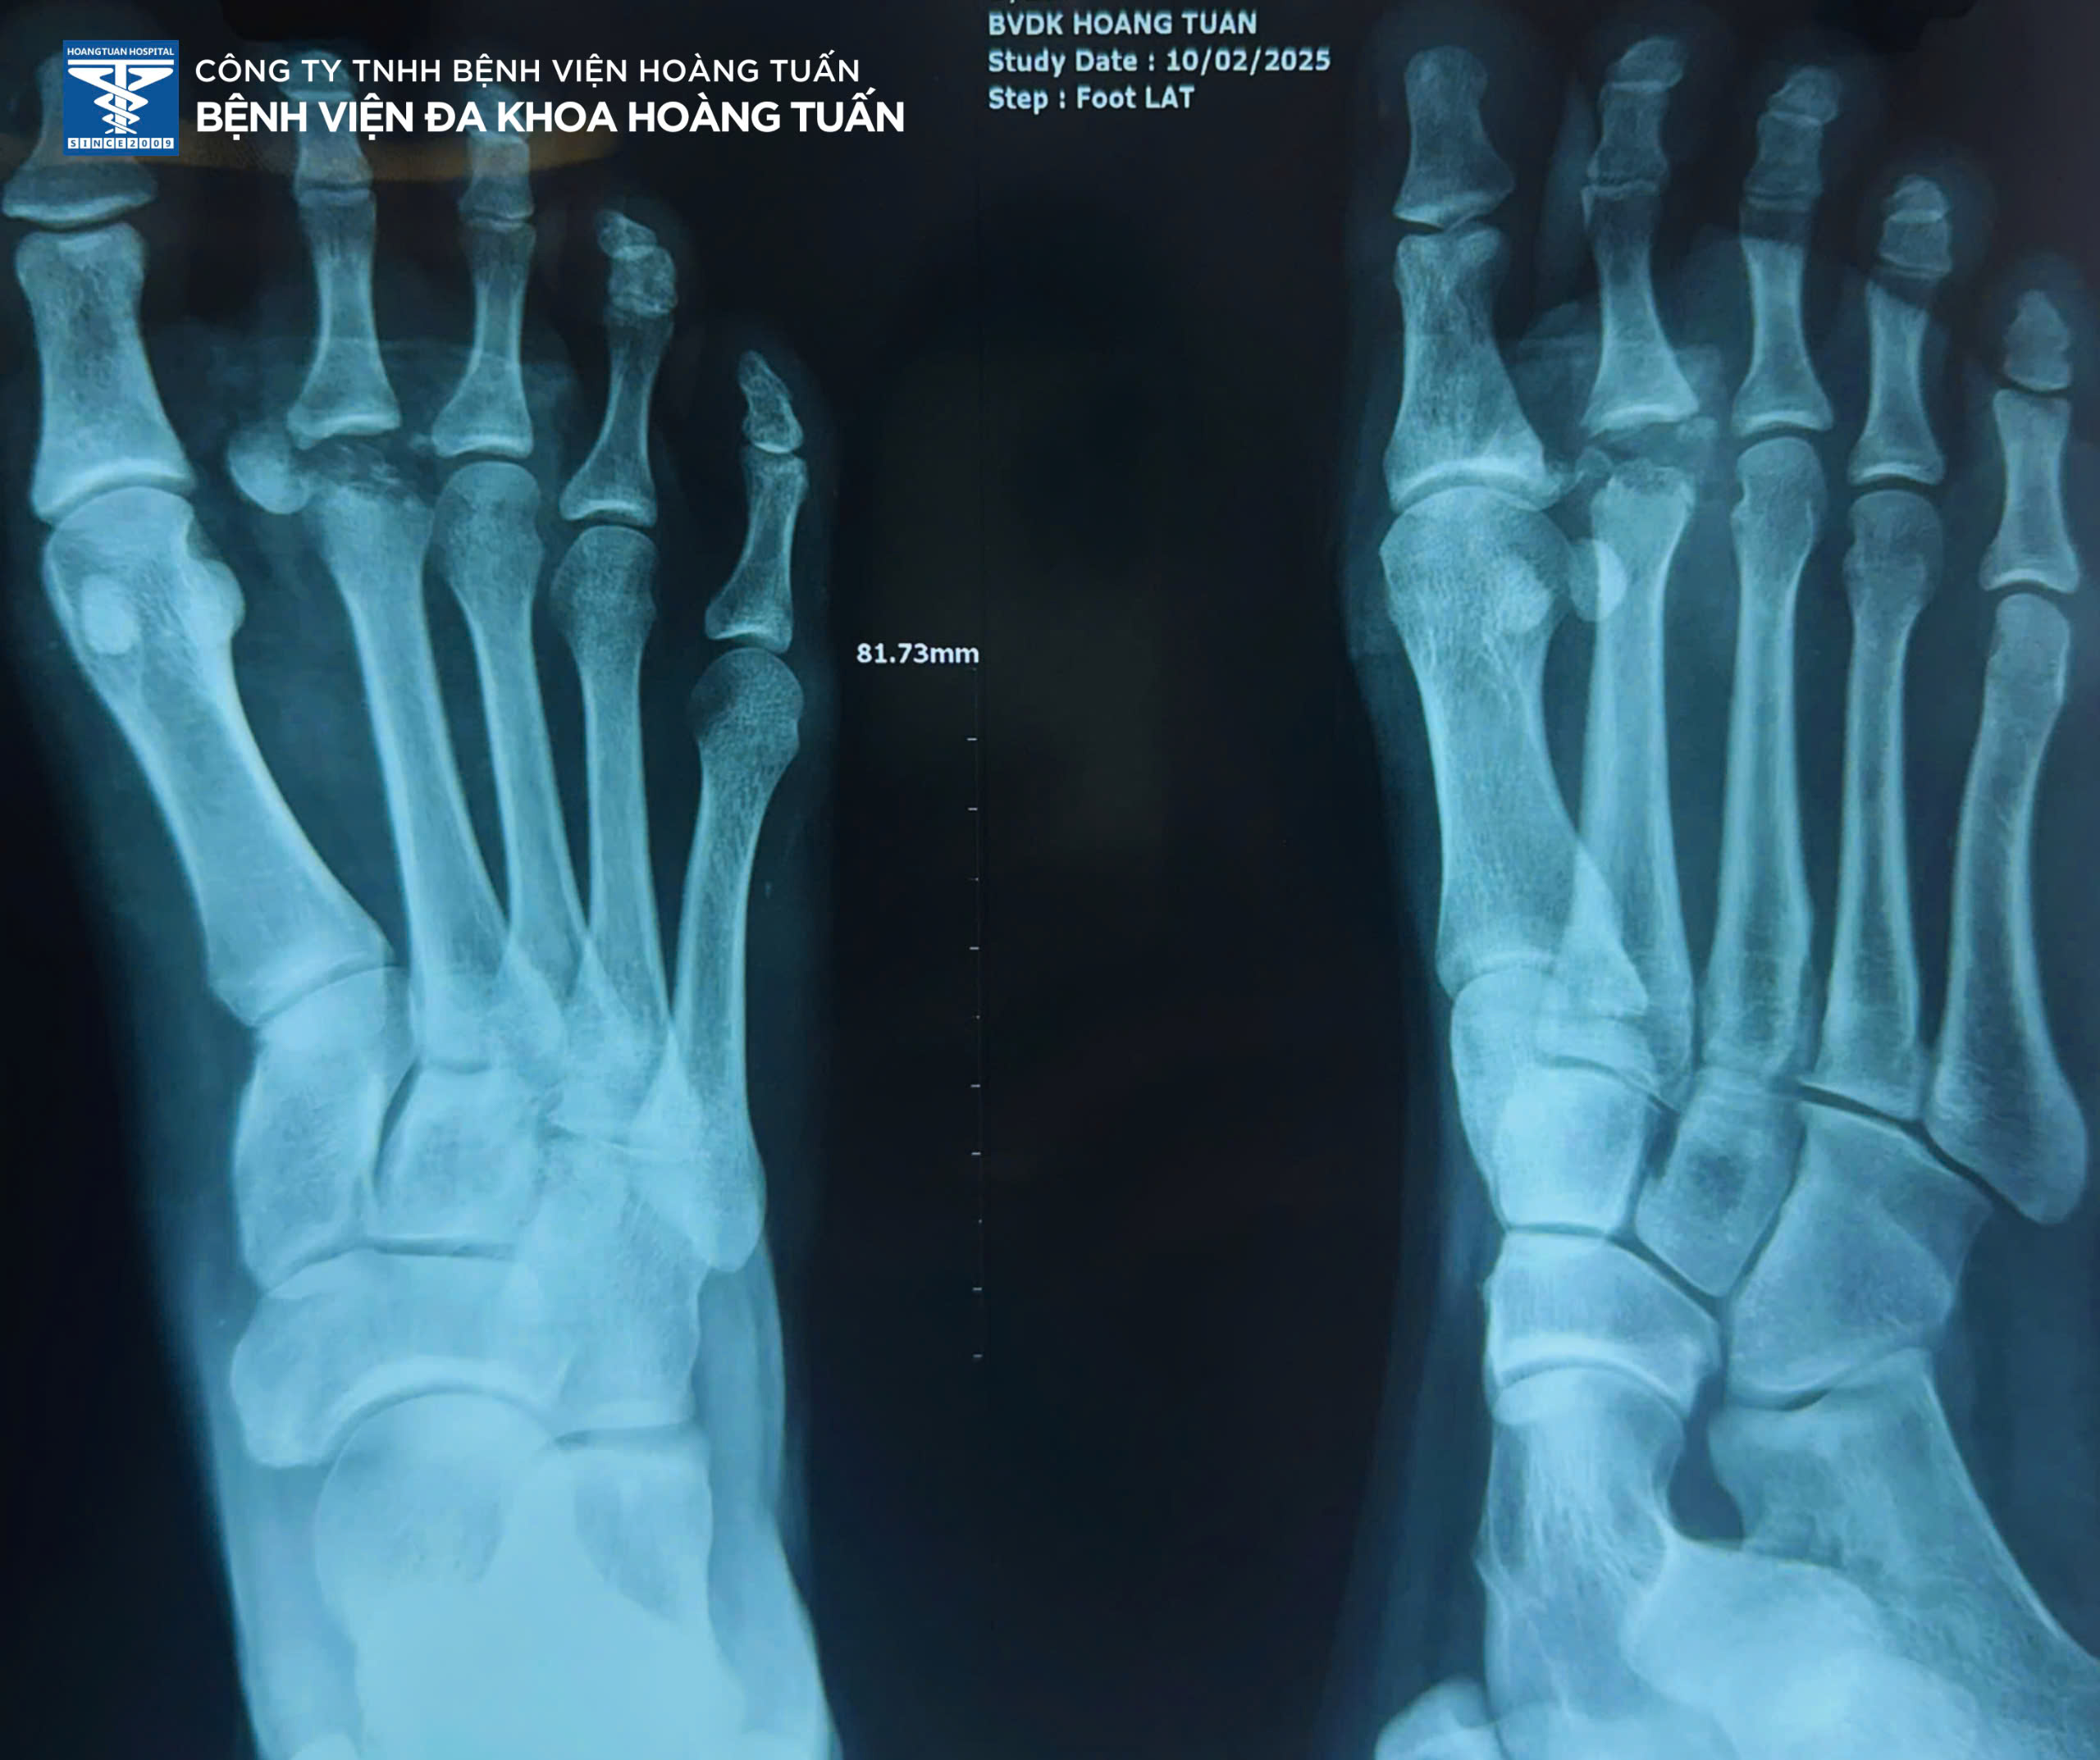

• Vừa qua, Bệnh viện Đa khoa Hoàng Tuấn vừa tiếp nhận một trường hợp bệnh nhân nữ trẻ tuổi vào viện vì đau, chảy máu nhiều vết thương vùng bàn ngón chân phải sau tai nạn giao thông. Qua thăm khám và chụp X-quang vùng bàn ngón chân phải kiểm tra, phát hiện gãy vùng xương bàn ngón II bên phải. Ban lãnh đạo Bệnh viện và Bác sĩ Ngoại Chấn thương hội chẩn và thống nhất quyết định phẫu thuật điều trị phục hồi vùng xương gãy.